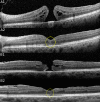

Purpose: To determine the prevalence of a central hyperreflective line in eyes with full-thickness macular holes (FTMH) and lamellar macular holes (LMH) and to elucidate the pathoanatomic importance of this optical coherence tomography (OCT) sign.

Methods: This retrospective analysis evaluated patients with FTMH and LMH at the Stein Eye Institute. Clinical data was collected and SD-OCT volume scans were analyzed for the presence of a central vertical hyperreflective line in 3 separate cohorts: patients with SD-OCT preceding FTMH development, patients with SD-OCT after pars plana vitrectomy (PPVT) treatment for FTMH, and patients with SD-OCT of LMH.

Results: In total, 93 eyes with FTMH and 88 eyes with LMH were identified. Of the 93 FTMH eyes, SD-OCT volume scans were available before development of the FTMH in 12 eyes. Of these, 6 (50%) displayed a vertical hyperreflective line preceding the development of the FTMH. Fifty-one eyes underwent PPVT with resolution of the FTMH, and 26 displayed a hyperreflective line after resolution (51%). Of the 88 eyes with LMH, 22 displayed a hyperreflective line (25%). All hyperreflective lines were noted at the central fovea.

Conclusions: SD-OCT illustrated the presence of a central vertical hyperreflective line preceding FTMH and after resolution of FTMH after PPVT in approximately one-half of cases, and concurrent with LMH in 25% of cases. This vertical hyperreflective line may represent an early SD-OCT marker for the development of FTMH, and may be a sign of central foveal dehiscence owing to disruption of the Muller cell cone.